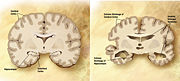

At a macroscopic level, AD is characterised by loss of neurons and synapses in the cerebral cortex and certain subcortical regions. This results in gross atrophy of the affected regions, including degeneration in the temporal lobe and parietal lobe, and parts of the frontal cortex and cingulate gyrus.

Both amyloid plaques and neurofibrillary tangles are clearly visible by microscopy in AD brains. Plaques are dense, mostly insoluble deposits of amyloid-beta protein and cellular material outside and around neurons that build up to insoluble twisted fibers within the nerve cell, often called tangles. Though many older people develop some plaques and tangles, the brains of AD patients have them to a much greater extent and in different brain locations.